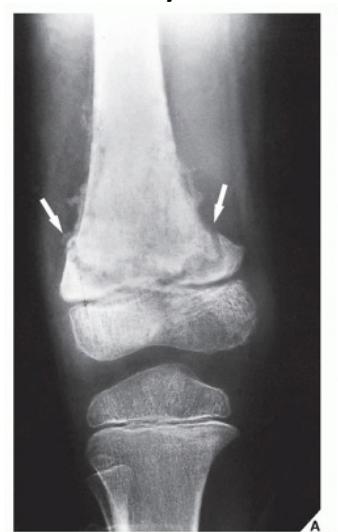

A teenager with acute onset of pain in the right hip during a run. He sustained the injury seen in the x-rays with a white arrow. This injury usually occurs due to a forceful eccentric contraction of which of the following muscles?

- C. Rectus femoris

- Sartorius

Pelvic Anatomy

Which of the following muscles is attached to the structure pointed by the arrow?

- C. Sartorius

Note: Arrow was pointing at ASIS (Anterior Superior Iliac Spine)